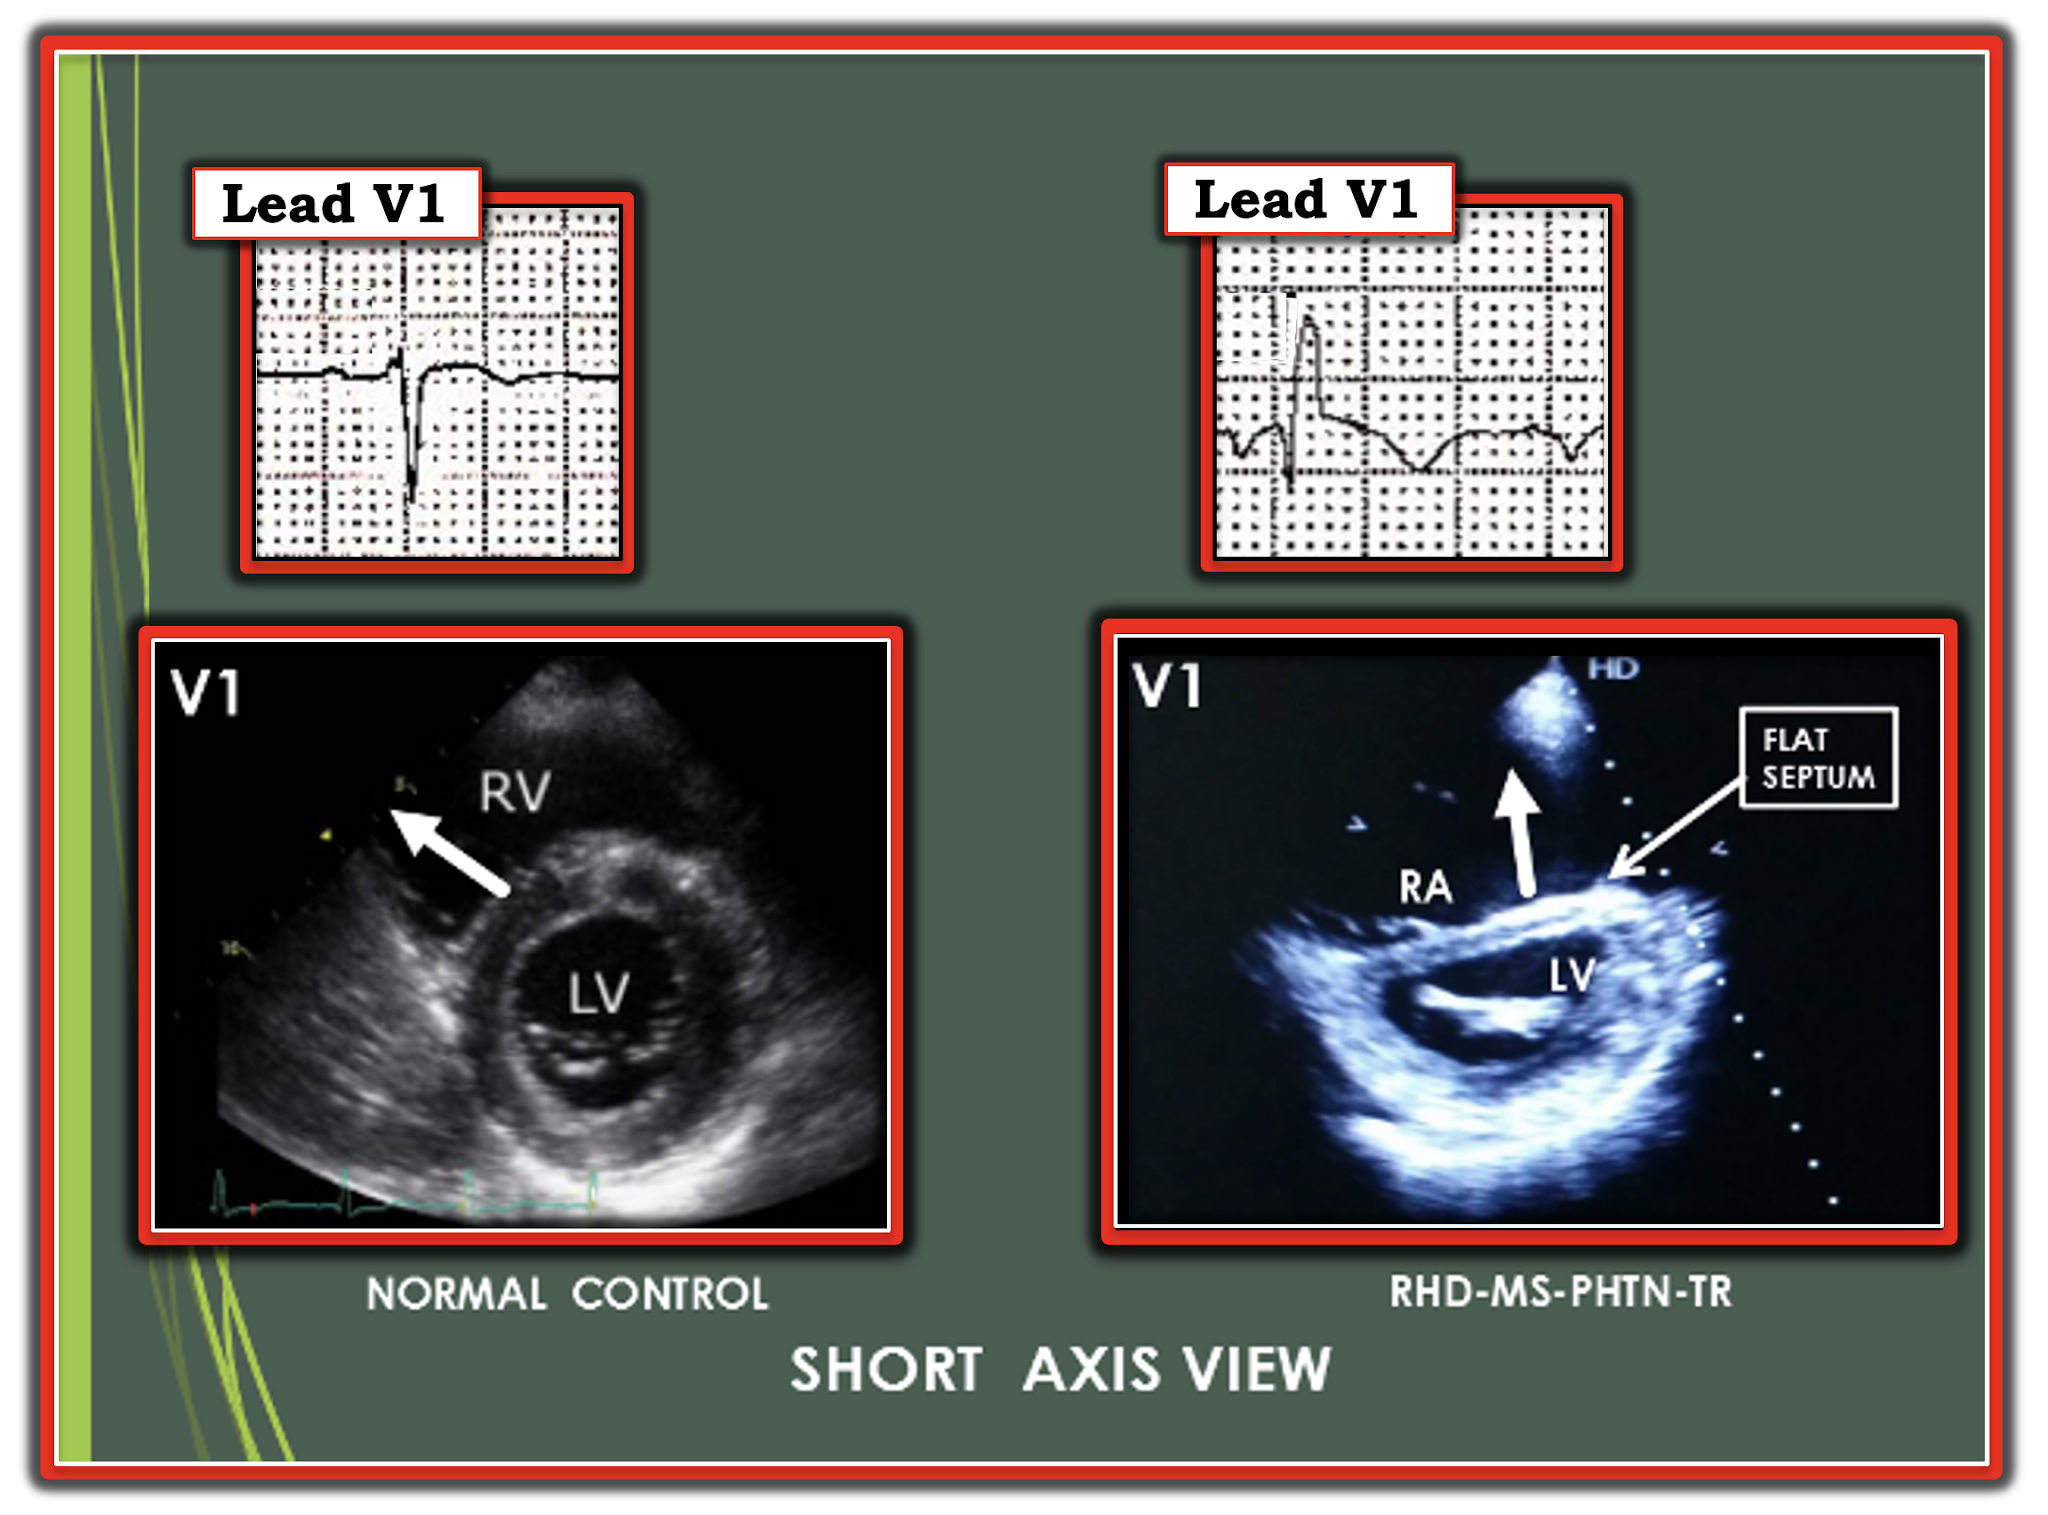

我們先來看看這張圖片

下方是Echo的PSAX view,左側是正常的,右側的PSAX view是因為出現RV dilate把Septum壓平,造成LV形成D sign。

在septum的電傳導正常會從septum的左側往右側放。所以我們看到在正常的狀況下,V1是接收到正面而來的電傳導,所以會先出現Upright的R wave。但是如果septum變形了(D sign+),當然放電還是從septum的左側往右側放。但是方向產生了變化。這個放電的向量不是正向朝著V1,而是有點離開V1。因此對於V1而言就會出現往下的Q wave,也就是Qr in V1。